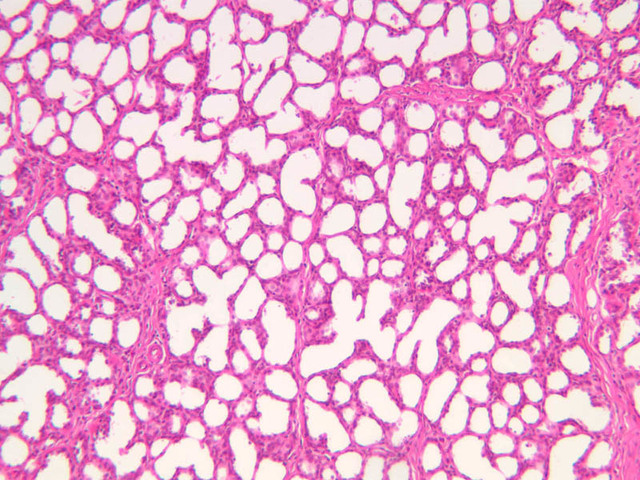

The mammary gland in its active state is a compound tubuloalveolar gland (slide A-92 [10x, 20x, 40x-labeled] [2.5x, 10x, 20x, 40x]; A-94 [2.5x, 10x, 20x, 40x]). At this time, the gland is predominantly glandular tissue. Each alveolus is lined by a simple cuboidal epithelium. At the base of these cells, and within the alveolar basal lamina, are the stellate-shaped myoepithelial cells that are highly contractile and function to facilitate milk ejection.

The resting or inactive mammary gland consists of predominantly dense connective tissue with small clusters of ducts and a few glandular elements (slide A-93 [2.5x-labeled, 10x, 20x, 40x] [1x, 2.5x, 10x, 20x]). It is difficult to differentiate between small ducts and alveoli as each is lined by simple low cuboidal cells. Lobes and lobules are not well defined. During puberty, predominantly under the influence of the ovarian hormone estrogen, the glandular or epithelial ducts proliferate and begin to differentiate into clusters of ductal and alveolar units termed terminal ductal lobule units (TDLUs). The non-pregnant gland will form multiple TDLUs that will not fully differentiate until pregnancy-induced growth. TDLUs are classified into Type I, Type II and Type III based on density of the ductules within each lobular unit. Type I and Type II lobules are typical of inactive glands that have not undergone a pregnancy cycle. Type III lobules are seen only in active glands or in inactive glands that have been through a pregnancy. Intralobular connective tissue is loose connective tissue that surrounds the alveoli and ducts within a lobule. The interlobular connective tissue is dense and contains considerable adipose tissue.

During pregnancy, predominantly under the influence of the ovarian hormone progesterone and the pituitary hormone prolactin, the glandular elements proliferate and differentiate to form milk-secreting units. In later stages of pregnancy, alveolar development becomes prominent and the amount of connective tissue and adipose tissue decreases. The secretory cells hypertrophy and accumulate secretory product.